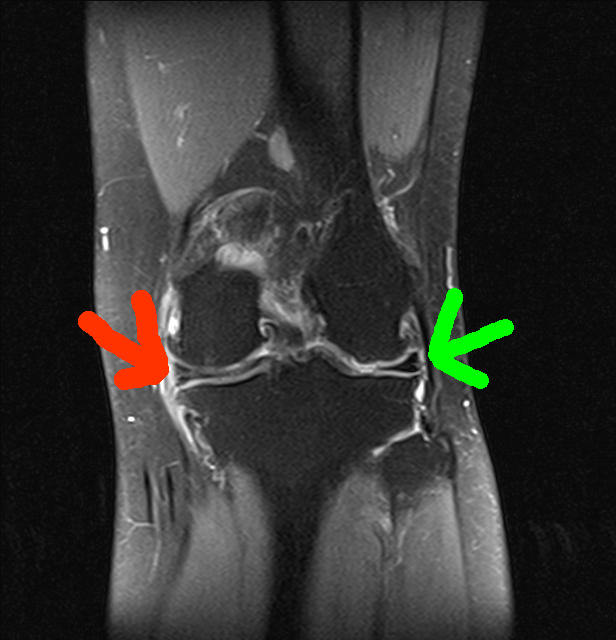

Der Innenmeniskus zeigt auf mehreren Bildern eine Auffälligkeit (Riss, rot markiert). Damals vor der Meniskus-OP am rechten Knie sah das MRT ähnlich aus, rechts ist der Außenmeniskus zu sehen (grüner Pfeil).

Die Kreuzbänder grüne Pfeile sind okay und ein bisschen Athrose (rote Pfeile) ist wohl auch dabei.